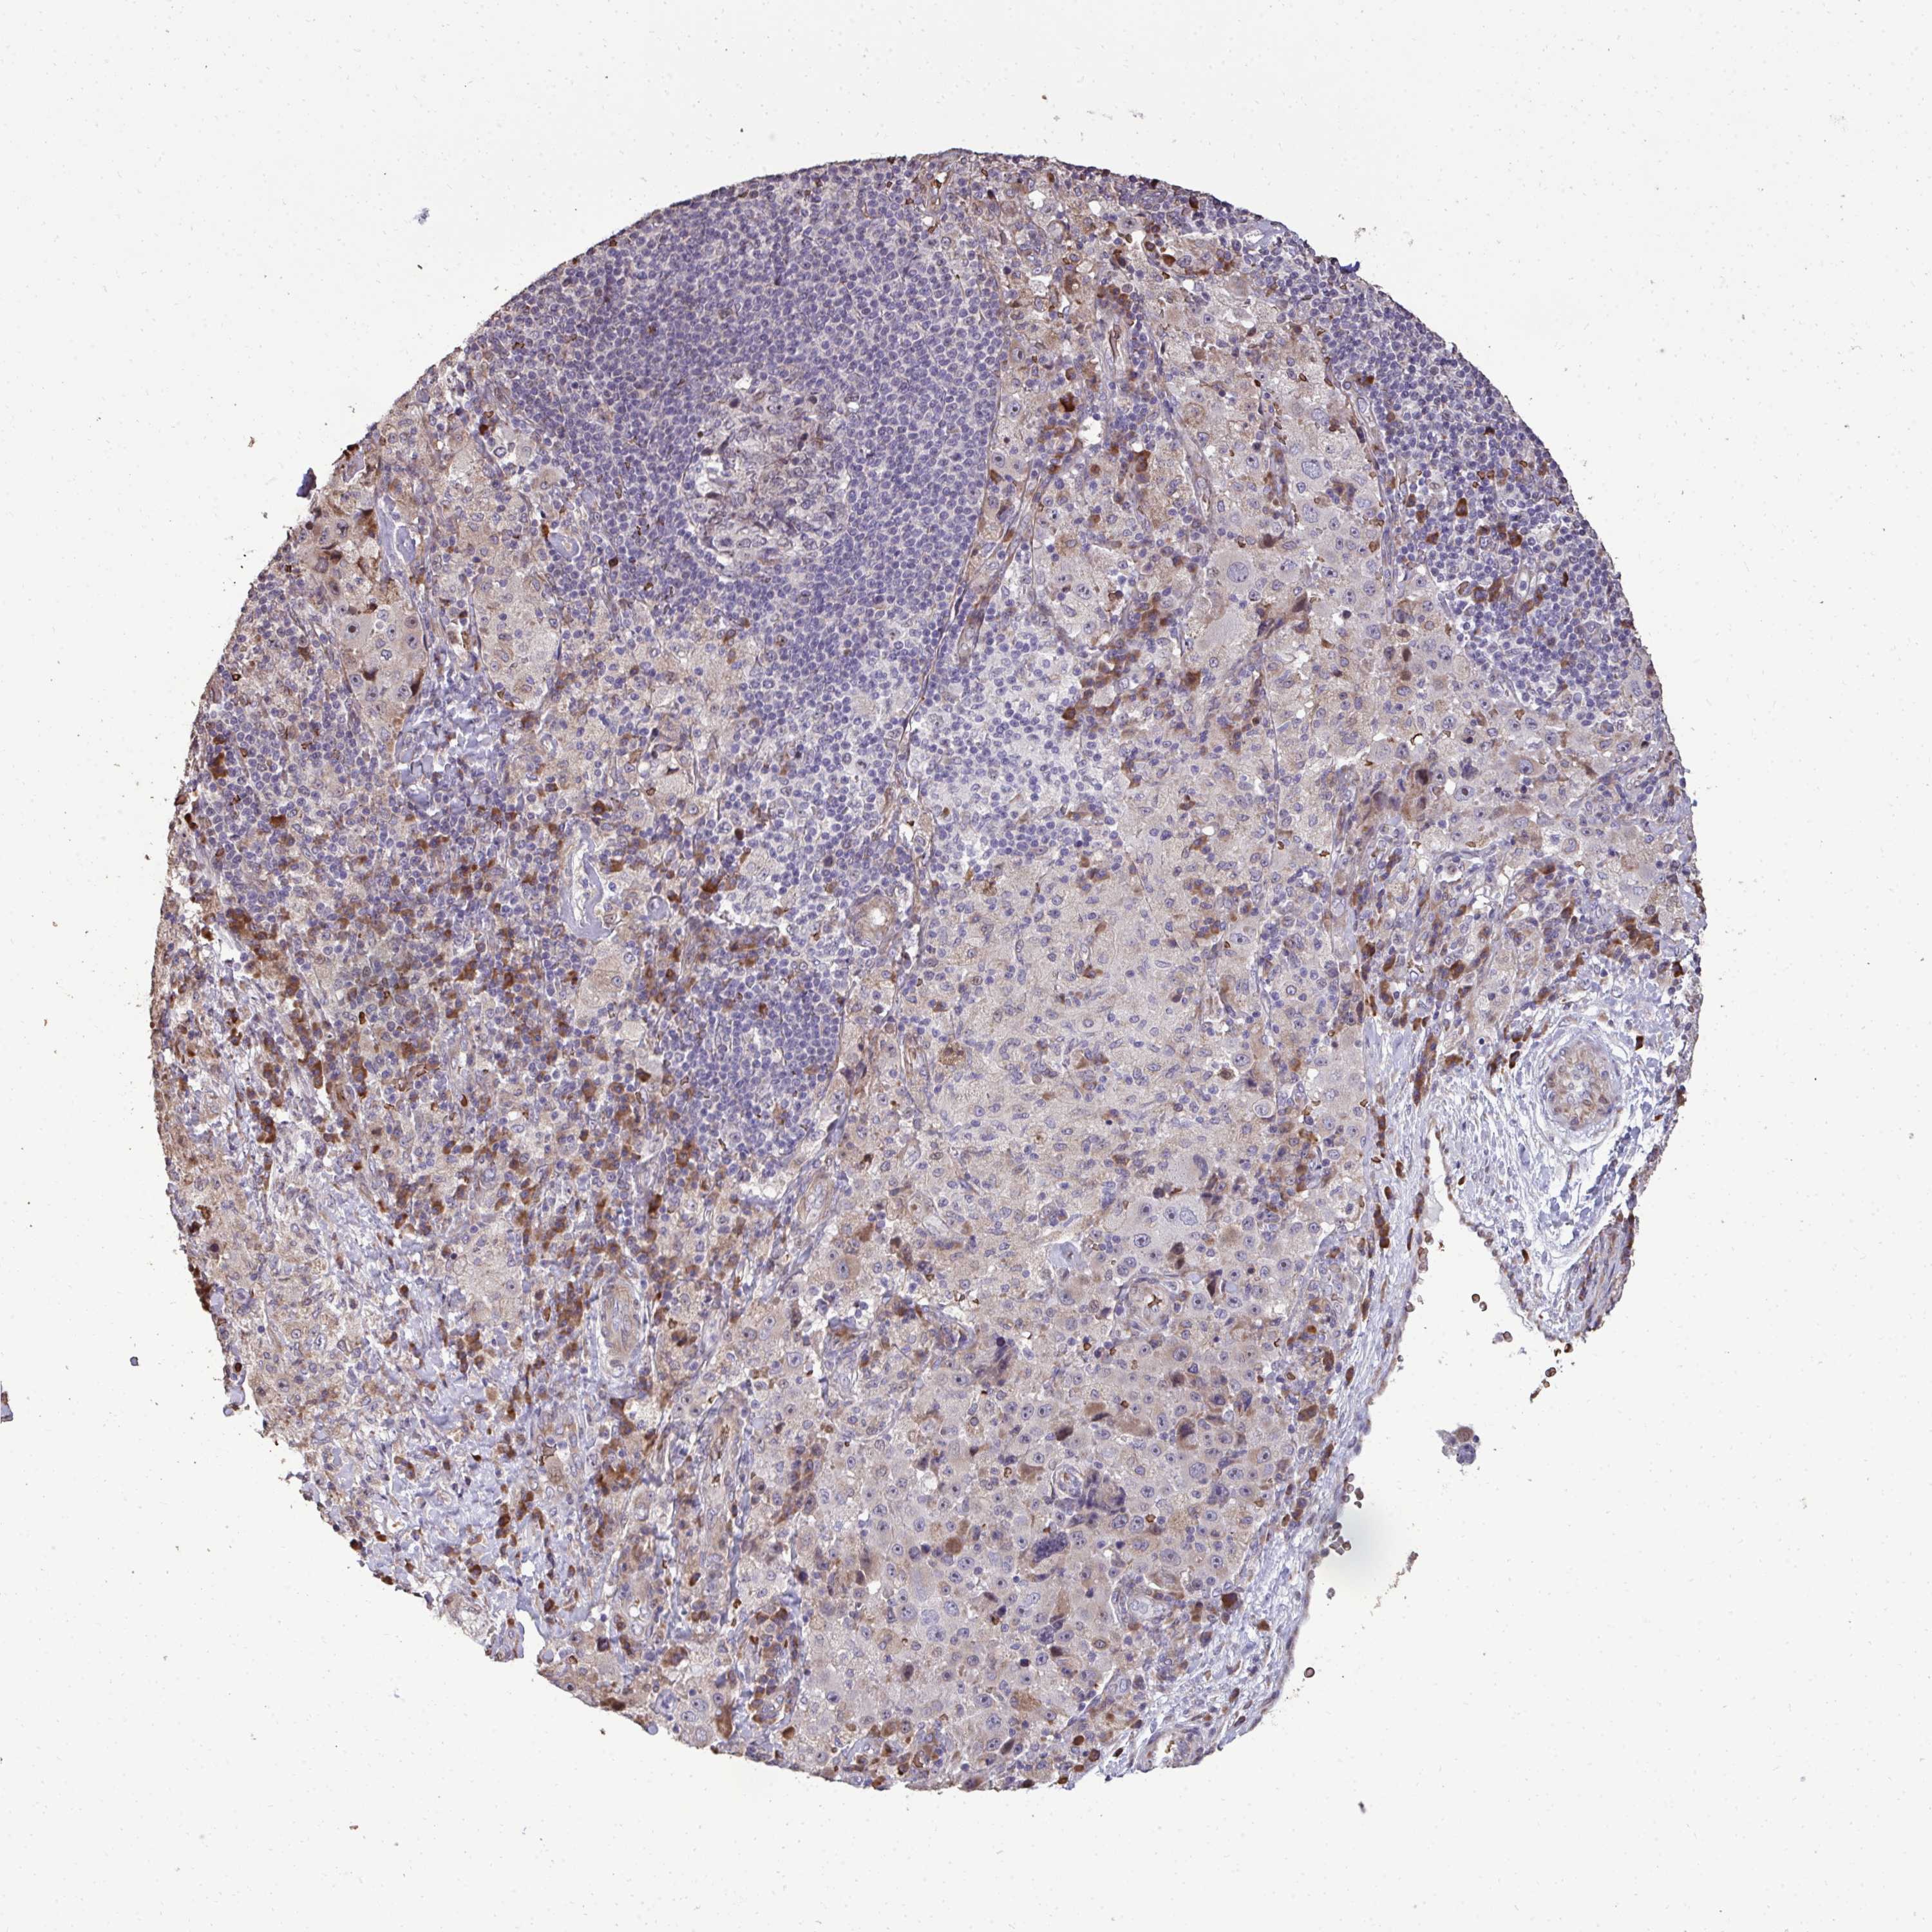

MELANOMA - Protein expressioni

A mouse-over function shows sample information and annotation data. Click on an image to view it in a full screen mode. Samples can be filtered based on level of antibody staining by selecting one or several of the following categories: high, medium, low and not detected. The assay and annotation is described here.

Note that samples used for immunohistochemistry by the Human Protein Atlas do not correspond to samples in the TCGA dataset.

Antibody stainingi

Antibody staining in the annotated cell types in the current human tissue is reported as not detected, low, medium, or high, based on conventional immunohistochemistry profiling in selected tissues. This score is based on the combination of the staining intensity and fraction of stained cells.

Each image is clickable and will lead to virtual microscopy that enables deeper exploration of all samples and also displays staining intensity scores, fraction scores and subcellular localization as well as patient and tissue information for each sample.

Antibody HPA055353

Staining

High

Medium

Low

Not detected

Intensity

Strong

Moderate

Weak

Negative

Quantity

>75%

75%-25%

<25%

None

Location

Nuclear

Cytoplasmic/membranous

Cytoplasmic/membranous,nuclear

Malignant melanoma, Metastatic site

Malignant melanoma, NOS